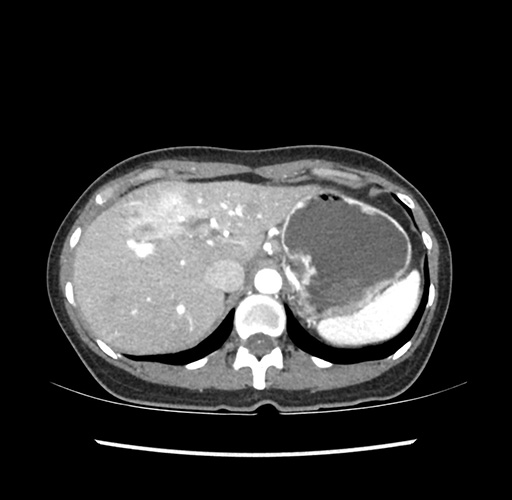

Imaging Analysis

Look through the patient's CT scan to identify any areas of concern for the necessary procedure.

Based on your CT findings, which issue(s) would give reason for "planned slowing down moment(s)" in this case?

Considering a standard left lateral sectionectomy procedure, what step(s) of the operation would you do differently in this case ?